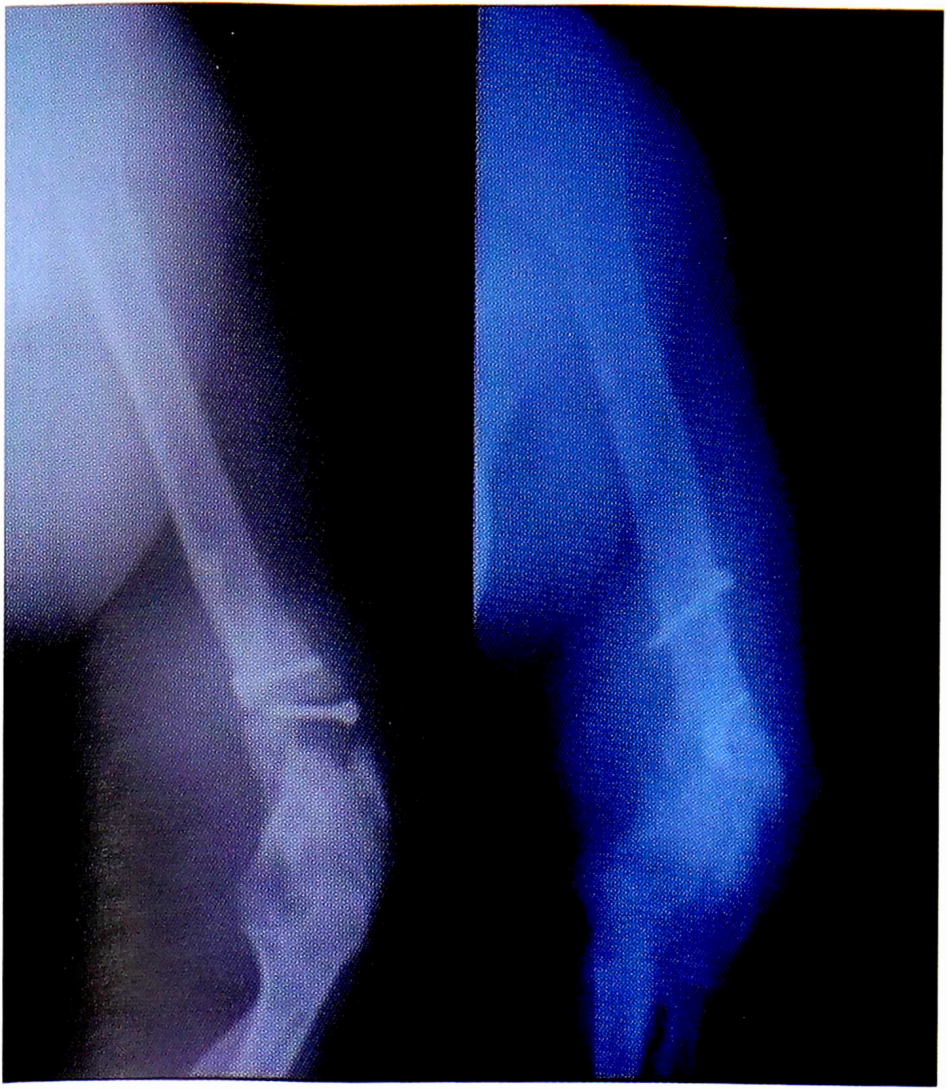

Рис. 3. Пациентка И.,34 лет. Внешний вид до операции.

Fig. 3. Patient 34 years old. Appearance before surgery.

Рис. 9. Внешний вид и функция через год после операции.

Fig. 9. Appearance and function one year after surgery.